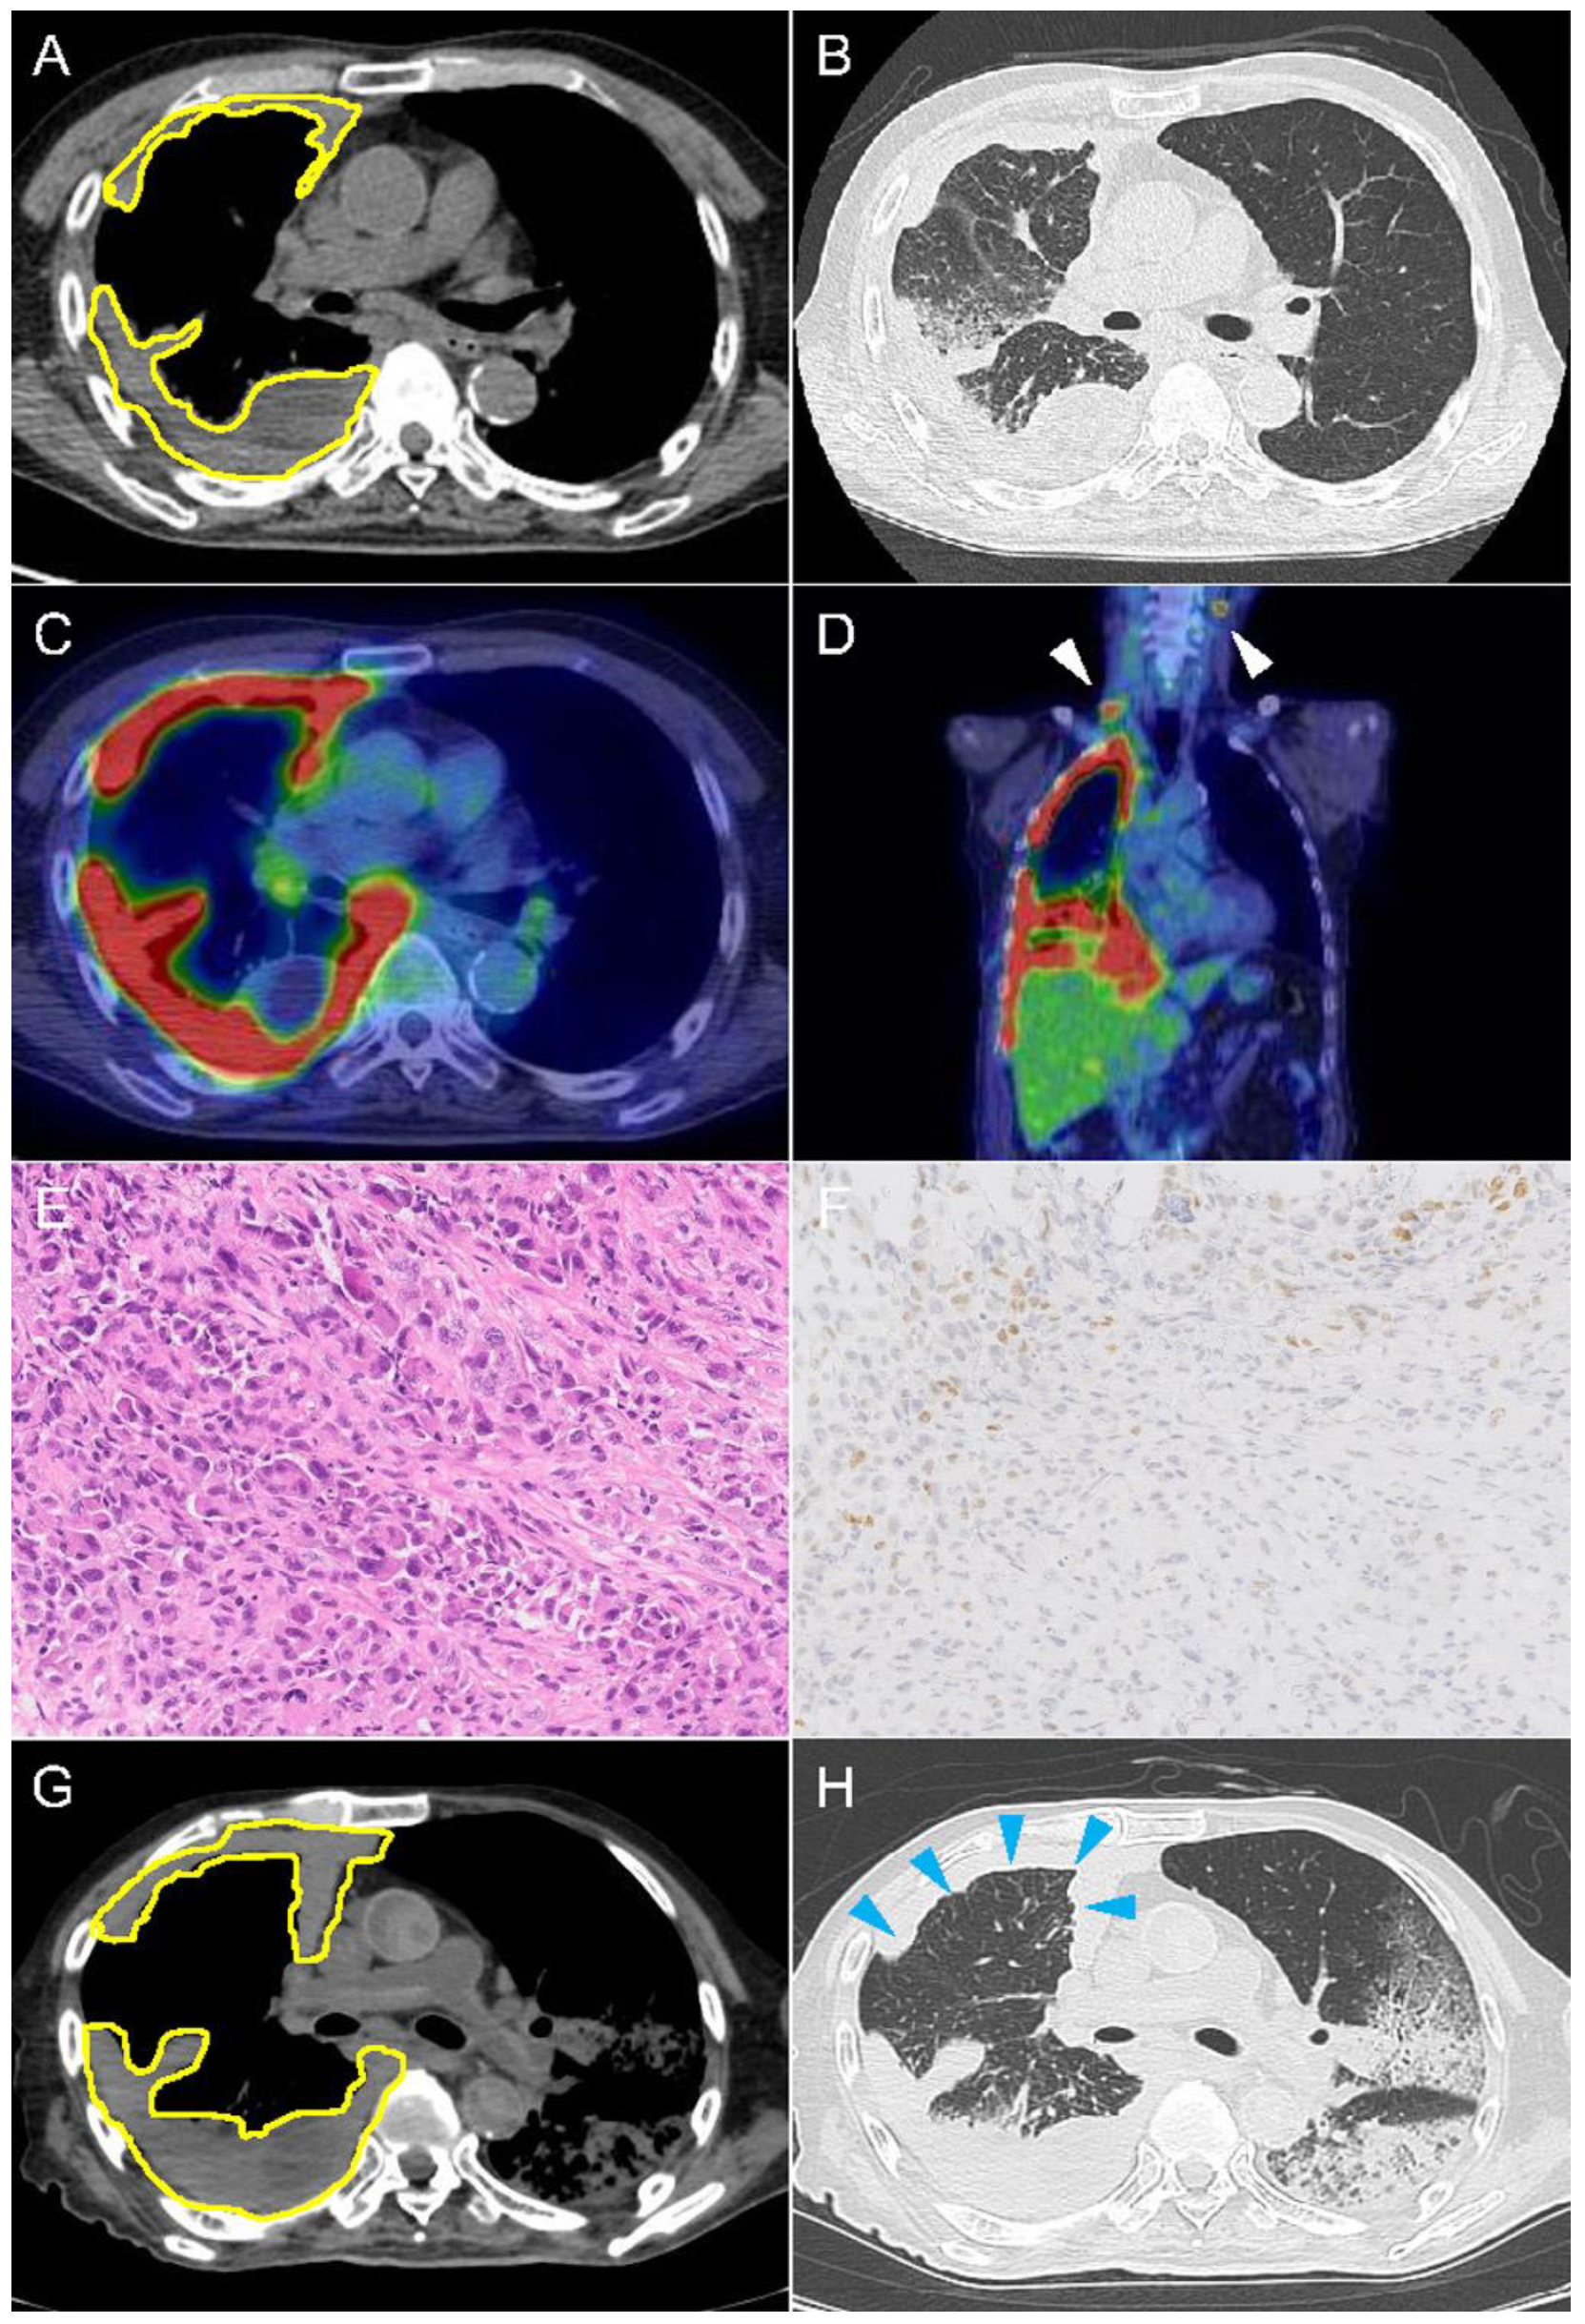

2.1. Case 1